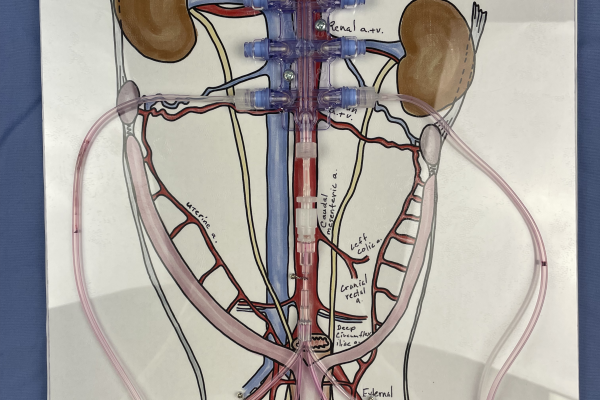

This model is used in an active learning activity for small animal anatomy. It is used to reinforce the anatomy and topography of the female reproductive tract in a clinically relevant context- an ovariohysterectomy (OHE)/spay surgical procedure.

Red fluid pushed by syringe through tubing mimics the collateral circulation servicing the uterus and ovaries in the cat and dog. String simulates the suspensory and round ligaments. Press’NSeal® secures the uterus, ovaries, vasculature, suspensory, and round ligaments within the broad ligament and secures it to the base in an anatomically correct position. Students apply plastic clamps to provide hemostasis at the ovarian pedicle and at the uterine body, as would be done in a spay procedure.

Ligatures can be applied and hemostasis checked when teaching more advanced clinical skills.